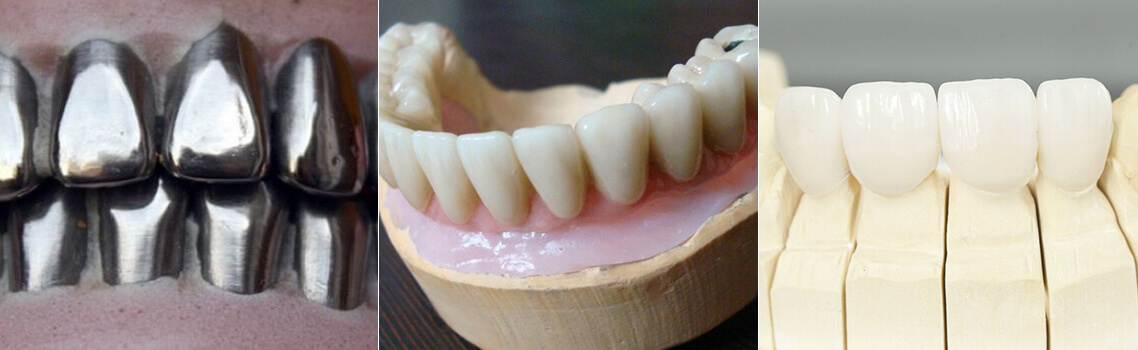

Современная стоматология: Железные зубные импланты